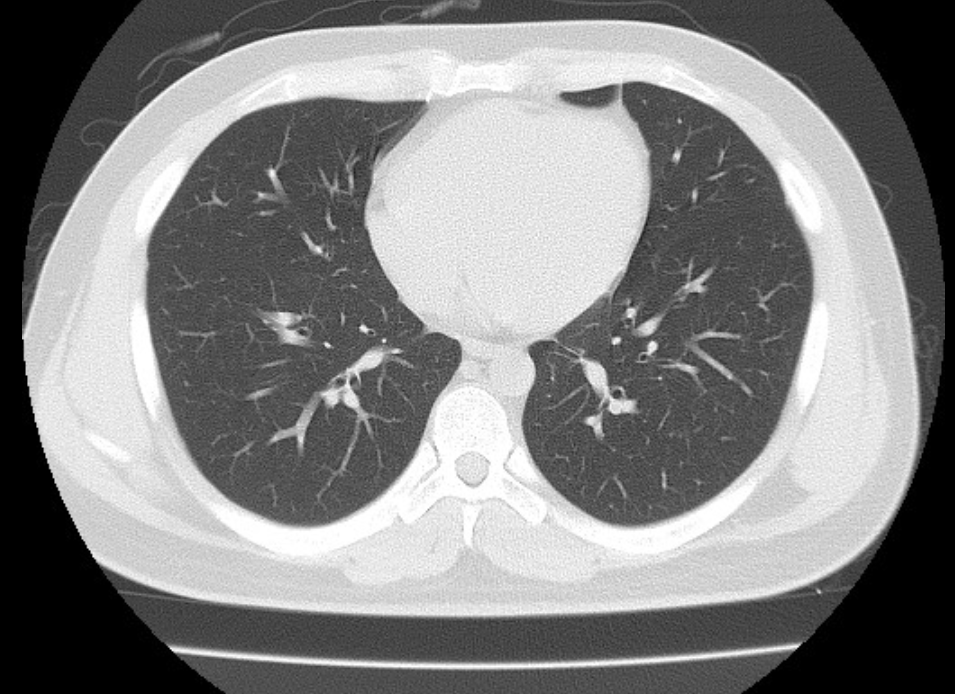

폐ct사진 받았는데 엄청 많더라구요.. 우중엽(40#)에 부분고형결절(6mm, 고형 2mm)결절이 있다고 소견을 받았는데 아래 ct사진 상 위험한 결절로 보이는지 판독좀 부탁드리겠습니다 ㅜㅜ. 다른 사진들 더 많지만 앞뒤 전후로 몇장씩만 가져왔어요..

• 1번 째 사진

밑에서 3번째 사진 우중엽 (보이기로는 왼쪽에 있는게 오른쪽 폐입니다)

흐릿하게 보이는 병변이네요

일반적으로 간유리음영과 결절이 같이 있을때 6mm 이상이면 암일확률이 1~2% 된다고 합니다. 저같으면 6개월후 추적검사를 해볼거 같네요